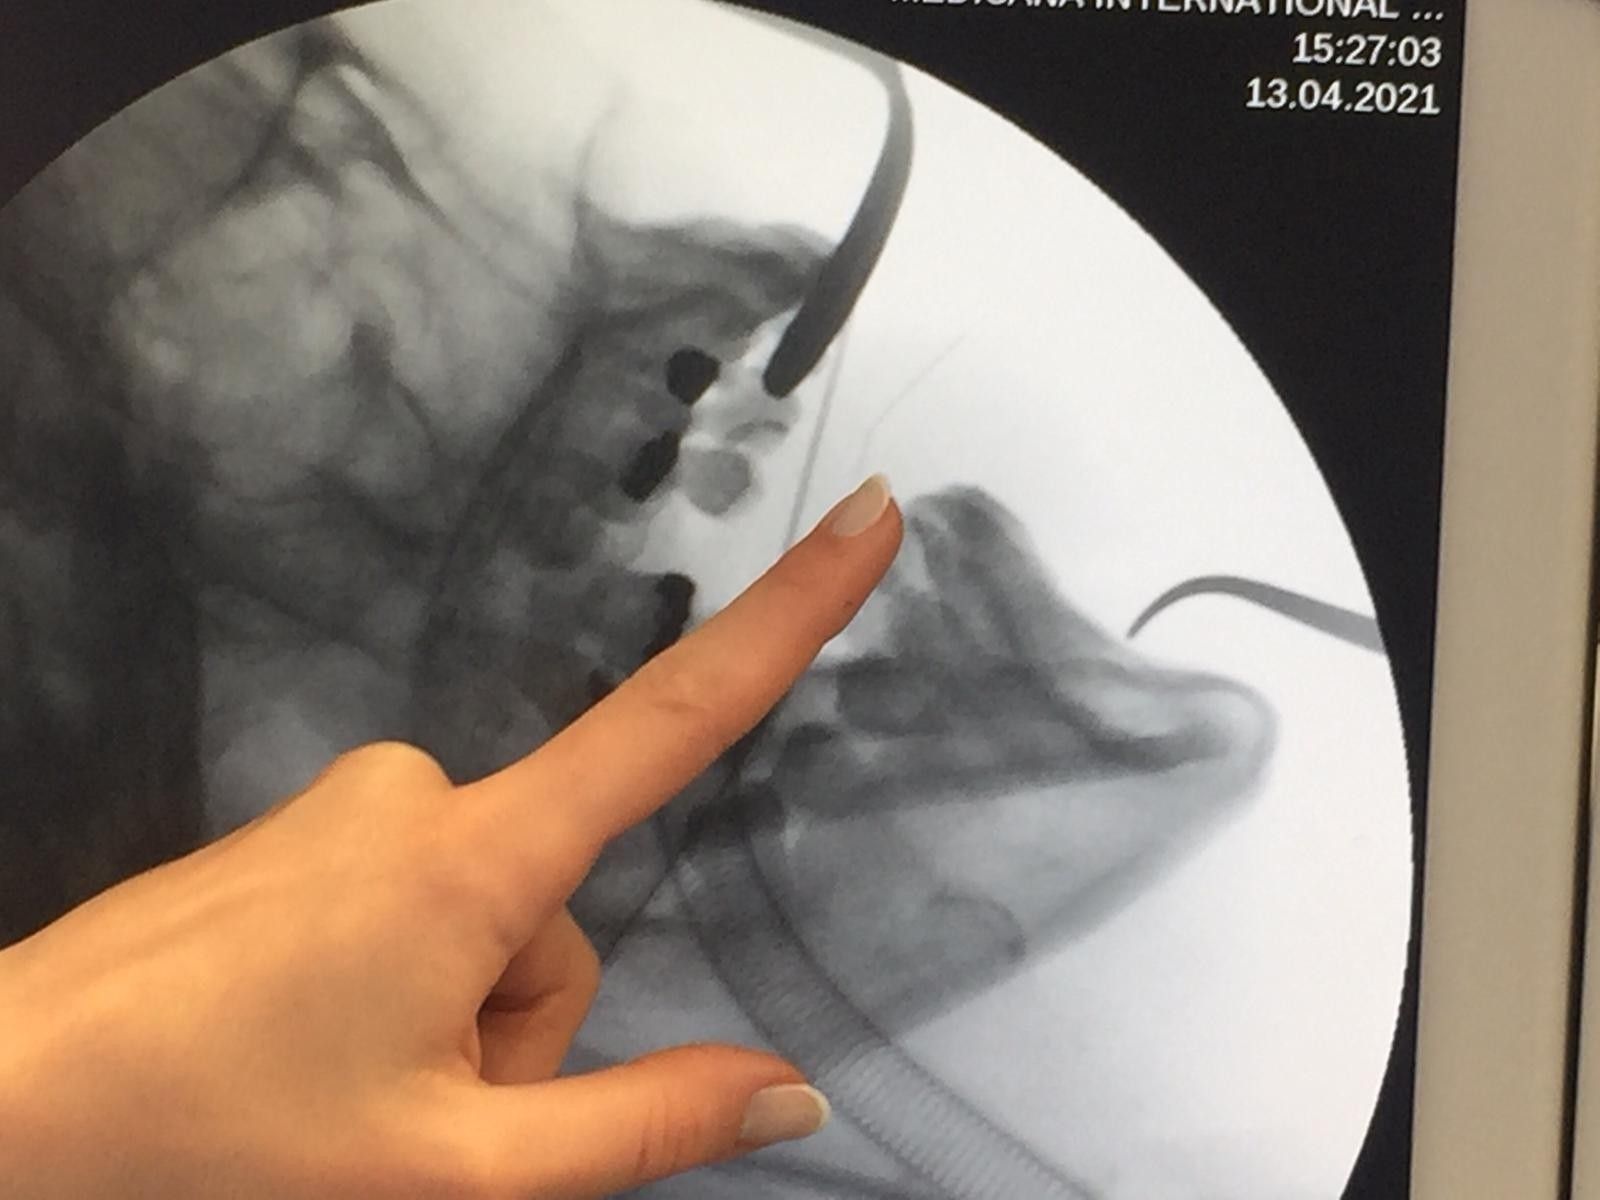

Dilin çok zorlu ve çok kanlı bir organ olduğunu ifade eden Prof. Dr. Ercan Pınar da, "Ben dilde, kürdan veya kıymık benzeri bazı cisimler çıkardım; ama metal iğne benzeri bir cisimle meslek hayatımda ilk kez karşılaştım. Hastamız daha önce yediği bir yemek esnasında diline batmış bu cisim. Fatma Hanım ağrı şikayetleri ile geldi bize ve çektiğimiz tomografi sonucunda dilin orta kısmında yüzeyde değil de derinde metal bir cisimle karşılaştık. Dil çok zorlu bir organ olduğu için cismi yerinde tespit etmek çok zordu o sebeple skopi eşliğinde iğnenin yerini tespit ettik. Daha sonra meslektaşım Prof. Dr. Murat Songu ile gerçekleştirdiğimiz operasyon ile dilin içinde derin bir kesi yaparak cismi çıkardık. Biz o cismi oradan almasaydık eğer orada bir enfeksiyon oluşabilirdi. Veya dil çok hareketli bir organ olduğundan ötürü cisim hareket edip ağız tabanına doğru hareket edebilirdi ve çok daha ciddi sonuçlara yol açabilirdi" ifadelerini kullandı.